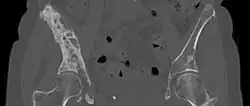

CT scan in the coronal plane of bone metastases of the hip bone, in a 60-year-old woman with parotid gland cancer. The more affected side is very irregular and sclerotic (visible as brighter in this presentation).